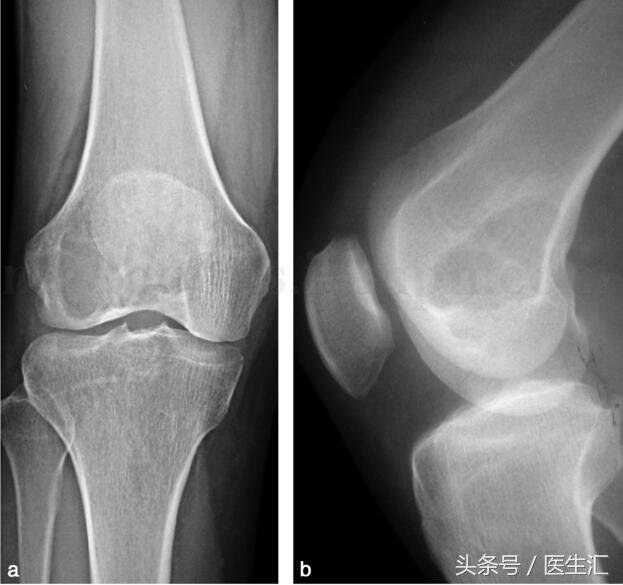

影像學(xué)檢查:X 線示右股骨遠(yuǎn)端骨端發(fā)生的一個(gè)偏心、基質(zhì)均勻、皮質(zhì)膨脹、皮質(zhì)無(wú)骨破壞、無(wú)骨膜反應(yīng)、無(wú)軟組織腫塊的溶骨性破壞(圖29‐1a,圖29‐1b)。CT 示右股骨遠(yuǎn)端骨端的溶骨性破壞,基質(zhì)均勻,注射造影劑后,病變強(qiáng)化,CT 值由強(qiáng)化前的40HU 增加到強(qiáng)化后的110HU(圖29‐2a~圖29‐2c)。

圖29‐1

a﹒右股骨下段外髁部溶骨性骨破壞(X 線正位片);b﹒右股骨下段外髁部溶骨性骨破壞(X 線側(cè)位片)